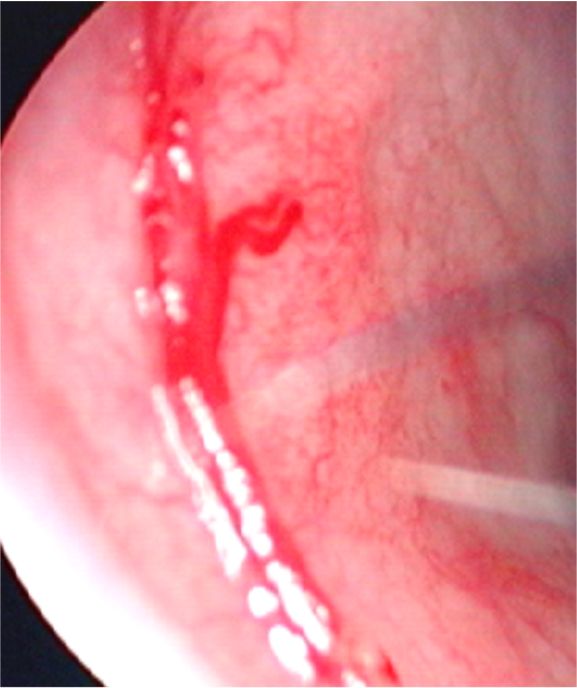

・アレルギー性鼻炎や慢性副鼻腔炎のある子どもでは、鼻の入り口がただれて、かゆいため、指を入れるのがクセになっていることが多く、この鼻中隔前方(キーゼルバッハ部位)の粘膜を傷つけて、出血がおこります。

・出血部位が明らかで、鼻の入り口近くのものは電気メスで痛んだ血管を凝固して止血します。